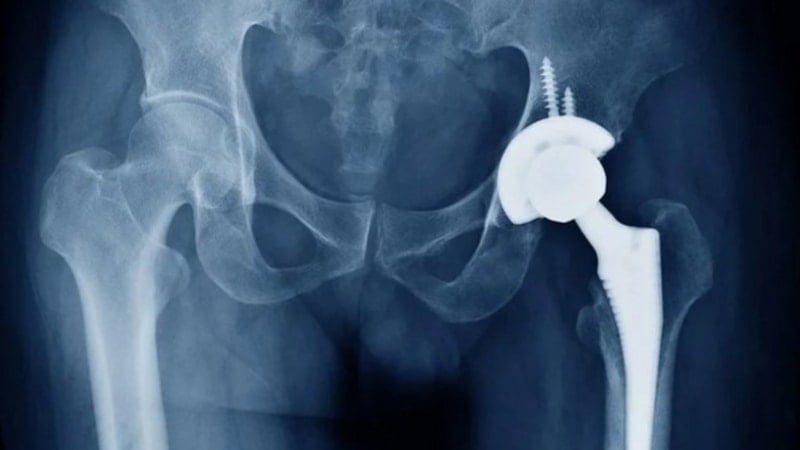

Ortopedi alanında geliştirilen yeni cerrahi alet, kalça protezi ameliyatlarında görüş alanını açık tutarak operasyonu daha güvenli ve kontrollü hale getirmeyi hedefliyor.

Kastamonu Üniversitesi bünyesinde geliştirilen yenilikçi bir cerrahi alet, ortopedi alanında önemli bir ihtiyaca çözüm sunuyor. Kalça protezi ameliyatlarında cerrahın görüşünü artıran ve operasyon sürecini kolaylaştıran sistem, resmi olarak tescil edilerek bilim dünyasına kazandırıldı.

Ortopedi ve Travmatoloji Anabilim Dalı öğretim üyesi Fatih Uğur tarafından geliştirilen alet, özellikle kalça protezi operasyonlarında karşılaşılan teknik zorlukları azaltmayı amaçlıyor. Sistemin en dikkat çeken özelliği, ameliyat sırasında cerrahın görüş alanını açık tutarak daha kontrollü bir çalışma imkânı sağlaması.

İki ana bileşenden oluşan cerrahi alet, yumuşak dokuları kontrollü şekilde uzaklaştırırken kemiğin pozisyonunu sabit tutabiliyor. Bu sayede protezin doğru açıyla yerleştirilmesi kolaylaşırken, operasyon sırasında oluşabilecek hataların da önüne geçilmesi hedefleniyor.

Uzmanlara göre kalça protezinin doğru konumlandırılması, hastanın ameliyat sonrası hareket kabiliyeti ve protezin uzun ömürlü olması açısından kritik önem taşıyor. Geliştirilen sistem, kemikte oluşabilecek pozisyon değişikliklerini anlık olarak fark etmeye yardımcı olarak yanlış yerleştirme riskini azaltıyor.